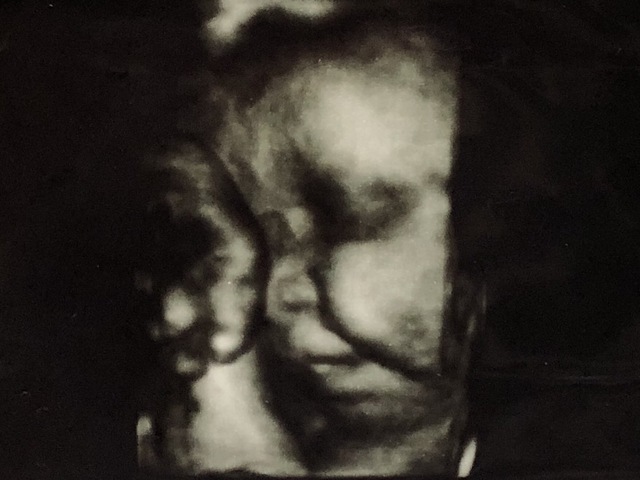

27週0日(27w0d・女の子)|kanna6210 さん(24歳)

エコー写真撮影時のエピソード:

はじめてはっきりくっきりした顔を見せてくれたときの写真です。

タイミングよく3Dでも顔が見れて感動しました!

いつも恥ずかしがって顔を隠していたので嬉しかったです!